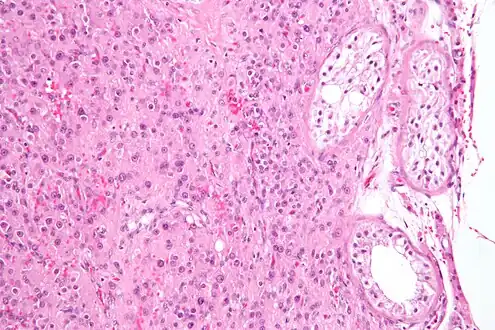

![]() Micrograph showing a cluster of Leydig cells (center of image). H&E stain. | |

Leydig cells, also known as interstitial cells of the testes and interstitial cells of Leydig, are found adjacent to the seminiferous tubules in the testicle and produce testosterone in the presence of luteinizing hormone (LH).[1][2] They are polyhedral in shape and have a large, prominent nucleus, an eosinophilic cytoplasm, and numerous lipid-filled vesicles.[3]

The mammalian Leydig cell is a polyhedral epithelioid cell with a single eccentrically located ovoid nucleus. The nucleus contains one to three prominent nucleoli and large amounts of dark-staining peripheral heterochromatin. The acidophilic cytoplasm usually contains numerous membrane-bound lipid droplets and large amounts of smooth endoplasmic reticulum (SER).[4] Besides the abundance of SER with scattered patches of rough endoplasmic reticulum, several mitochondria are also prominent within the cytoplasm. Reinke crystals have lipofuscin pigment and rod-shaped crystal-like structures 3 to 20 micrometres in diameter.[5]